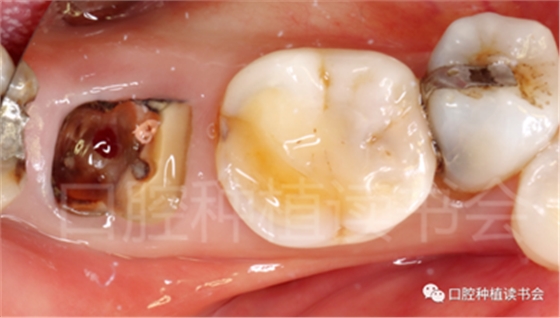

5.3.9 術后第6周,47行種植2期手術,可見種植體周圍愈合良好,牙齦成型后,旋入愈合基臺(圖22)。

圖22 種植體周圍獲得了良好的骨整合。